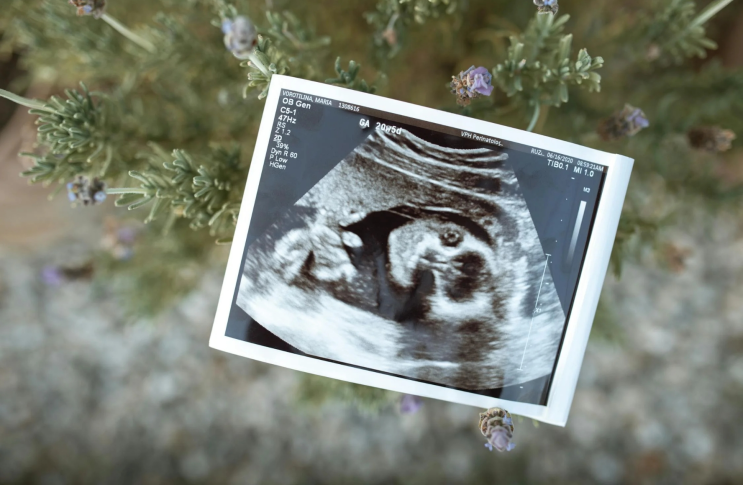

태아 성별 확인 시기! 12주 각도법 정확도는?

임신 초기부터 자연스럽게 궁금해지는 태아 성별! 미리 확인할 수 있는 다양한 방법들이 있죠 ㅎㅎ 오늘은 ...